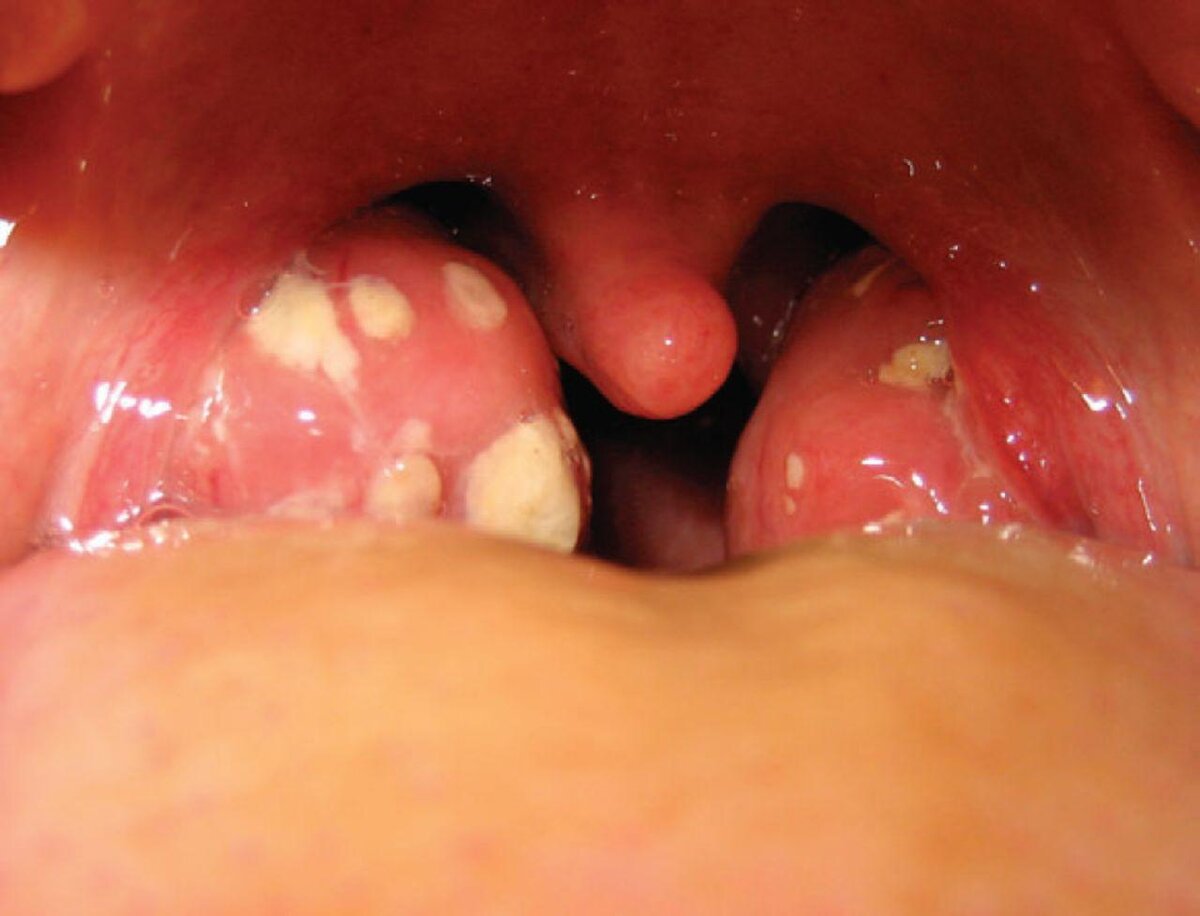

Тонзиллит — это инфекционное заболевание, поражающее одну или несколько миндалин, чаще небных, вызванное бактериальной или вирусной инфекцией. Основным симптомом тонзиллита является боль в горле. Это страшное заболевание